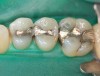

Figure 7. Three defective amalgams and cracks on the first molar and bicuspids.

Figure 7

Case 2 (Figure 7 through Figure 11) depicts a series of defective amalgams on the first molar and biscupids. The amalgams were removed, the decay was excavated and cracks were eliminated. Bonding was completed on dentin and enamel. The teeth were matrixed and composite was built with layering techniques. To control contours, each tooth was completed individually, and then the next one was done. Composite was shaped, occlusal adjustment was completed, and final polishing was done.